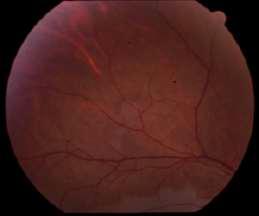

4.A. RETINOPATÍA POR LEUCEMIA MIELOIDE AGUDDA

Imágenes aportadas por Dra. Cavieres

Imagen A y B:

ü Hemorragias en llamas

ü Focos blancos algodonosos

ü Manchas de Roth

ü Las manifestaciones típicas de la leucemia reflejan el cuadro general de anemia o pancitopenia, con hemorragias intrarretinianas e infartos de la capa de fibraas nerviosas (manchas algodonosas). Dentro de las hemorragias tenemos las ”manchas de Roth” que corresponden a hemorragias intrarretineanas con centro blanco

ü En ocasiones puede encontrarse infiltración leucémica de la retina, de la papila óptica o de la coroides, normalmente en la región peripapilar

ü Puede haber compromiso neuroftalmológico como edema de papila por hipertensión intracraneana cuya diferencia con la infiltración directa esta dada por la toma de AV o DPAR

ü En estos paciente siempre se debe descartar compromiso secundario por infecciones oportunistas

Yannuzzi L “Leucemia” Atlas de la retina, editado por Lawrence A Yanuzzi Elservier ediciones 2011 págs 729-736

A B